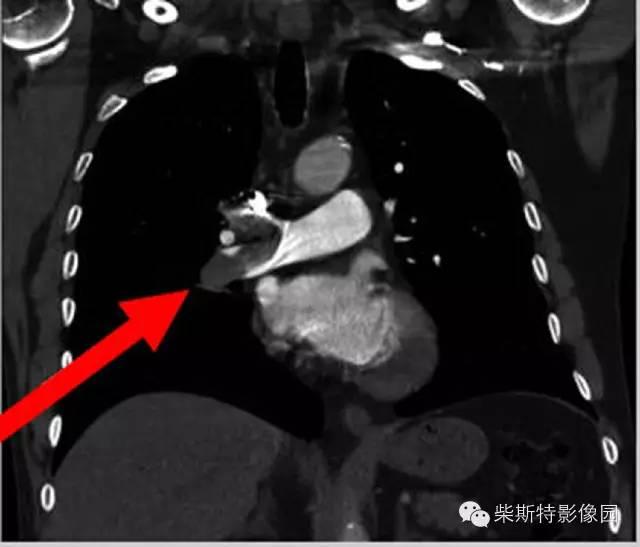

第二大名捕:肺动脉CTA

红色箭头所指处即栓塞导致的充盈缺损,从横断位、冠状位、矢状位三个层面观察,造影剂为高密度白色,而栓子的存在导致造影剂无法充填,从而表现为黑色的低密度影。俗话说的好:长江后浪推前浪!肺动脉CTA的本领已经基本超越其“大哥”肺动脉造影!还可以估测房室大小!